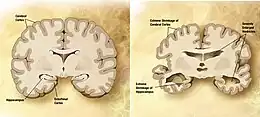

Atrophie corticale

La maladie d'Alzheimer est caractérisée par une perte de neurones et de synapses dans le cortex cérébral et certaines régions subcorticales. Cette perte anormale entraîne une atrophie des régions affectées, incluant le lobe temporal, pariétal et une partie du Lobe frontal et du gyrus cingulaire[61]. Le cerveau peut ainsi perdre 8 à 10 % de son poids tous les dix ans, contre 2 % chez un sujet sain. L'atrophie corticale s'accompagne d'une dilatation des ventricules cérébraux et des sillons corticaux ainsi que d'une perte neuronale affectant particulièrement le système cholinergique (noyau basal de Meynert, septum, cortex entorhinal, amygdale et hippocampe).

Les études utilisant l'IRM et le PET scan ont documenté une réduction de certaines régions spécifiques chez les personnes atteintes de la maladie d'Alzheimer lorsqu'elles progressent d'un trouble cognitif léger vers une maladie d'Alzheimer, en comparaison des images de sujets sains âgés[62],[63].

Effets des lésions selon la localisation

Selon les endroits touchés par les lésions causées par la démence d'Alzheimer, les résultats seront différents :

- l'atteinte de l'hippocampe joue sur les processus de mémorisation : enregistrement, restitution et organisation des souvenirs;

- les lésions au lobe frontal occasionnent des troubles des fonctions exécutives[64];

- les lésions au cortex postérieur provoquent aphasie, agnosie et apraxie ;

- l'atteinte du système limbique a des conséquences sur les émotions, les liens entre souvenirs et comportements, le sommeil et l'appétit[64] ;

- les lésions à la formation réticulée occasionnent des problèmes de vigilance et des troubles du sommeil.